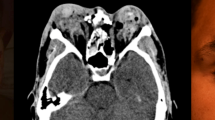

Thirty eyes were included: 15 (50%) were males with a mean age of 47 (±28) years. All presented with zone 1 injury. Twenty-five (83%) had a perforated corneal ulcer. Presenting VA was count fingers (n = 3, 10%) to NLP (n = 6, 20%). Twenty-four (80%) involved infection, 5 (17%) congenital, 3 (10%) chemical burn and 2 (7%) neurotrophic. Conjunctival injection (n = 22, 77%), corneal opacification (n = 20, 71%) and relative afferent pupillary defect (n = 9, 44%) were common. After treatment, 23 (88%) were worse than 6/60 (20/200), 9 (35%) were NLP and 8 (27%) required enucleation.

Often non-traumatic open globe injuries are zone 1 and due to perforated infectious ulcers. Compared to previously reported traumatic injuries, these have higher rates of enucleation (27% vs 8%) and poorer final VA (88% vs 68% worse than 6/60 20/200).